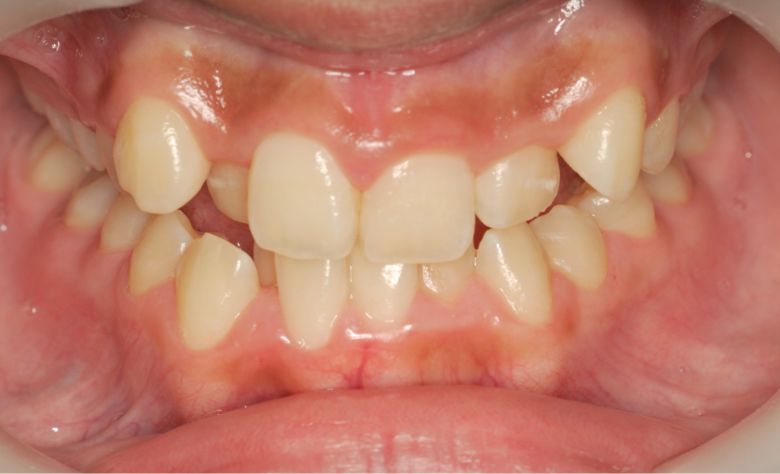

上下ともに歯並びが乱れており、噛み合わせにも大きな不調和が見られる

他院にて上下左右4本の抜歯を前提とした矯正治療を提案されていました。上顎・下顎ともに歯列弓が狭く、

V字型の弓状を呈していたため、叢生(歯の重なり)が強く、噛み合わせにも不調和が見られる状態でした。

上下の咬合関係も不正で、機能的にも審美的にも問題のある状態でした

歯列全体に強いガタつき(叢生)が見られ、特に上下の前歯は重なりが大きく、見た目にも咬み合わせにも

大きな不調和がありました。歯列弓はV字型に狭く、他院では抜歯を伴う矯正治療が提案されていました。

上下の前歯に強い重なりが見られます。特に上顎犬歯と下顎前歯のズレが顕著で、自然な咬合が形成されていない